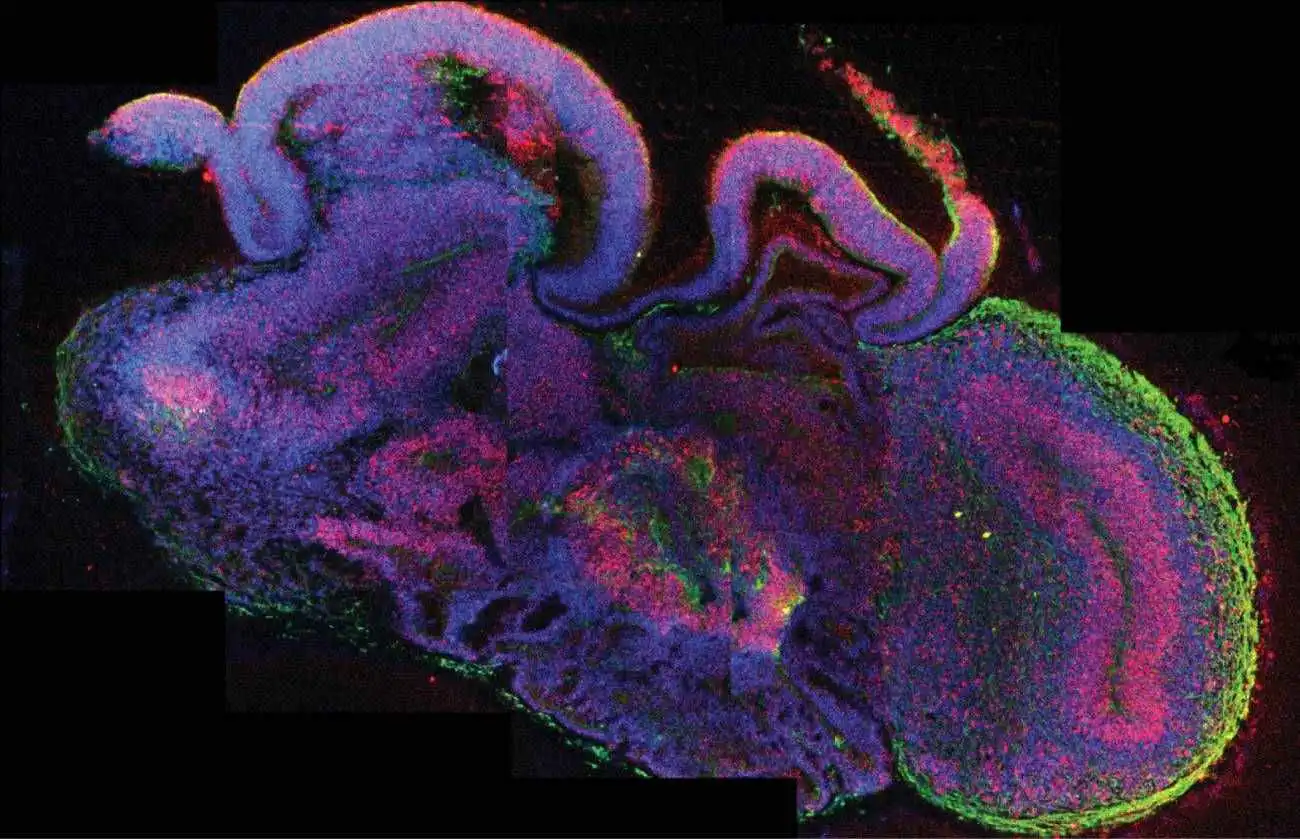

Investigadores de la Universidad Johns Hopkins han creado en laboratorio pequeños cerebros humanos que imitan varias regiones clave del cerebro real. Estos “mini cerebros”, llamados MRBO, no solo reproducen partes como el cerebro anterior o el tallo cerebral, sino que además presentan actividad eléctrica organizada y una red vascular incipiente, lo que los hace más parecidos que nunca a un cerebro humano en desarrollo.

A diferencia de modelos anteriores, estos organoides integran múltiples zonas cerebrales y un sistema vascular básico, lo que los hace más parecidos a un cerebro humano real. Incluso comienzan a formar una barrera hematoencefálica, clave para probar medicamentos.